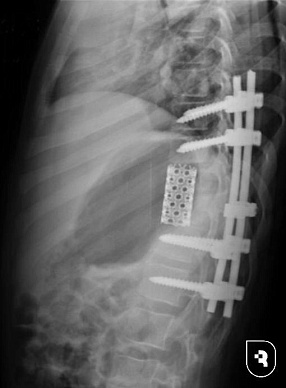

После подтверждения диагноза и исключения поражения других органов, врачи приняли решение о сложнейшей трехэтапной операции. Перед этим мальчику назначили терапию для борьбы с паразитами. На первом этапе медики выполнили левостороннюю торакотомию, удалили эхинококковую кисту и частично два позвонка. Затем исправили деформацию позвоночника с помощью специальной системы, после чего провели вторую операцию на грудной клетке и установили протез позвонка.